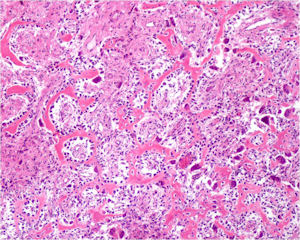

Microscopic Pathology

- Interlacing network of bone trabeculae in a loose fibrovascular stroma

- Prominent vessels

- Osteoblasts are plump, active, scattered mitotic figures

- Osteoblasts line up around periphery of trabeculae (Osteoblastic Rimming)

- Soft tissue component usually surrounded by shell of reactive bone or periosteum (Egg Shell Rim of Calcification)

- No cartilage production (as opposed to osteosarcomas that may contain areas of cartilage)